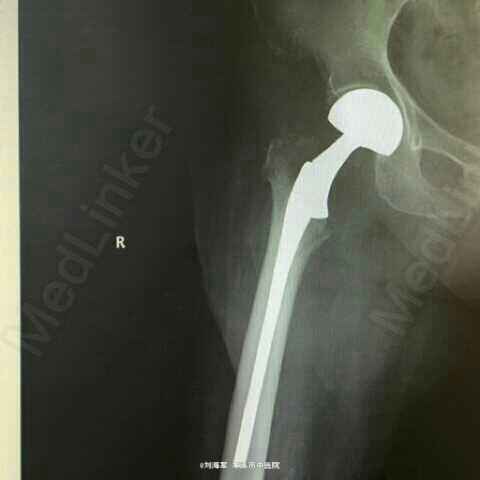

诊断:右股骨颈基底部骨折 治疗:行人工股骨头置换术

现住院中,有待随防